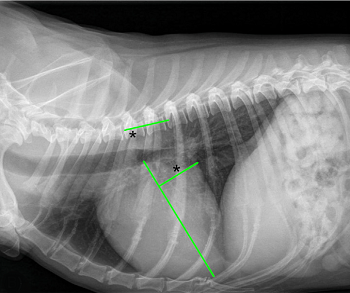

• VHS measurements to detect enlargement

Cardiologists use x-rays to evaluate the size and shape of the heart in

The Vertebral Heart

Size or Scale or Sum (VHS) is an objective means of measuring

the x-ray image above shows, using calipers, they

measure the length (from the apex to the bottom of the left mainstem) and width

(at

its widest point perpendicular to the lemgth measurement) of the heart

on a lateral x-ray and compare those dimensions

to the number of veterbrae from T4 to T12, to calculate the VHS value. Since

the dog's own vertebrae are used for comparison, each VHS value is

normalized to the dog's overall body size.

The VHS is not intended to diagnose CHF. It's purpose is to enable veterinarians to more accurately determine enlargement of the heart (called cardiomegaly or dilation) and the progression at which the enlargement is occurring, which usually is due to MVD. However, since MVD normally initially causes only the left atrium (LA) to enlarge, the VHS method is not precise enough to measure only the size of the LA. See for example, the x-ray at left, which shows that the VHS measurements entirely miss the bulbous enlarged LA in the upper right corner of the heart. (Image from Hezzell, 2018.)

The VHS method is most effective when it is used to compare two x-rays of the same dog's heart, taken over time, to see if the later x-ray's VHS value is higher than the earlier one, thus indicating that an enlargement of the heart has occurred. Therefore, once an MVD murmur is first detected, it is advisable to obtain an initial set of chest x-rays (called a "baseline" set) for comparison with subsequent x-rays once progression of the MVD is suspected.

An increase in VHS value of >0.1 per month over six months or more, in combination with a VLAS value >3.0, (see VLAS below) is evidence that the patient's heart has enlarged enough to classify it in Stage B2.